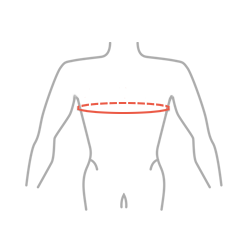

| Rozmiar | Obwód klatki piersiowej | Sposób dokonywania pomiaru |

| Uniwersalny | min 70 – max 135 cm |  |

Całkowita długość elementu ramienia: 35 cm